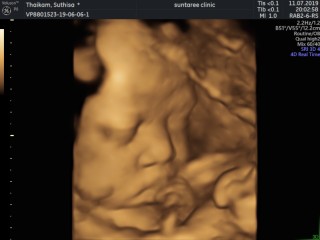

อัลตร้าซาวด์ 4 มิติ

แม่ๆคนไหนซาวด์4มิติบ้างคะ เอารูปมาอวดกันหน่อยค่ะ

ซาวด์ตอน 27 สัปดาห์คะ ไม่ยอมหันหน้า